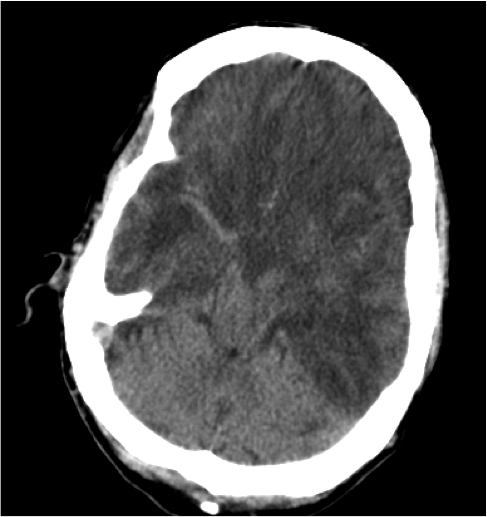

Hematoma Subdural.

- Se localiza entre la duramadre y la aracnoides y suele ser de origen venoso por la disrupción de venas corticales.

- Puede localizarse en punto de golpe y también en el de contragolpe.

- Semiluna hiperdensa (si agudo). Localización: Convexidad > hoz > tentorio

- Cuando son subagudos pasan a ser Isodensos, se identifican porque hay separación del cortex respecto a la tabla interna y efecto masa sin «masa aparente»: colpaso ventricular, desplazamiento de la línea media, etc.

- En estadío crónico puede ser hipodensos.

- Puede cruzar suturas.

- Puede asociar fracturas, contusiones, efecto masas, edema cerebral, HSA.